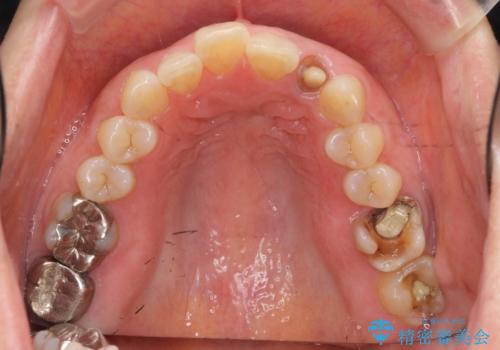

- 「 銀歯が原因で皮膚にアレルギー症状が出ている。」、と皮膚科のかかりつけ医に言われメタルフリー治療を希望され来院されました。

拡大鏡下で丁寧に銀歯の除去を行ったのち、金属を用いないセラミックインレー・クラウンによる治療を行います。